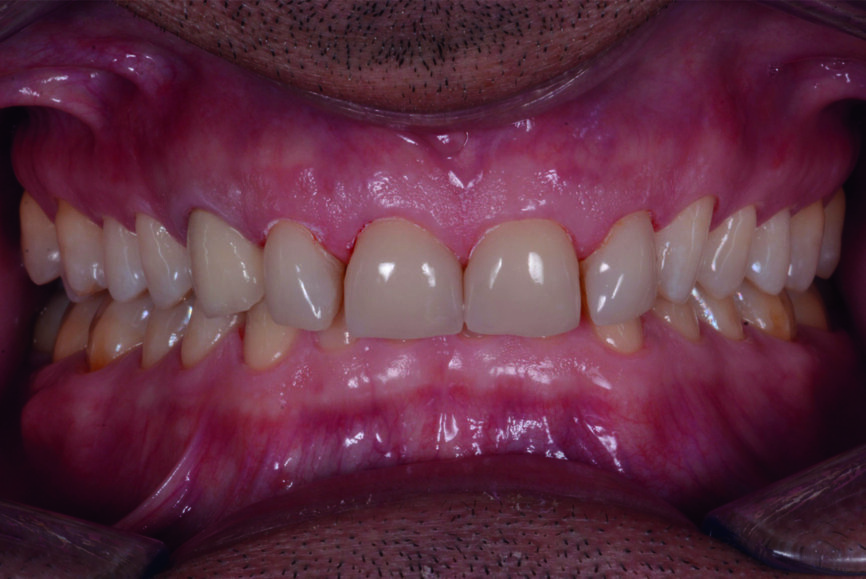

Figs. 13 et 14 : Photographies intraorales après le traitement.

Après l’élimination de l’excès de colle composite, l’occlusion est adaptée et vérifiée à l’aide du système d’évaluation occlusale T-Scan (Tekscan). Une contention amovible en résine acrylique est utilisée pour protéger les restaurations définitives, et celles-ci sont vérifiées six mois plus tard. À ce moment, les restaurations sont toujours stables et ne présentent aucun signe de fracture (Figs. 13–15). Le patient déclare également qu’il n’a plu souffert de maux de tête grâce à cette nouvelle dimension verticale d’occlusion.